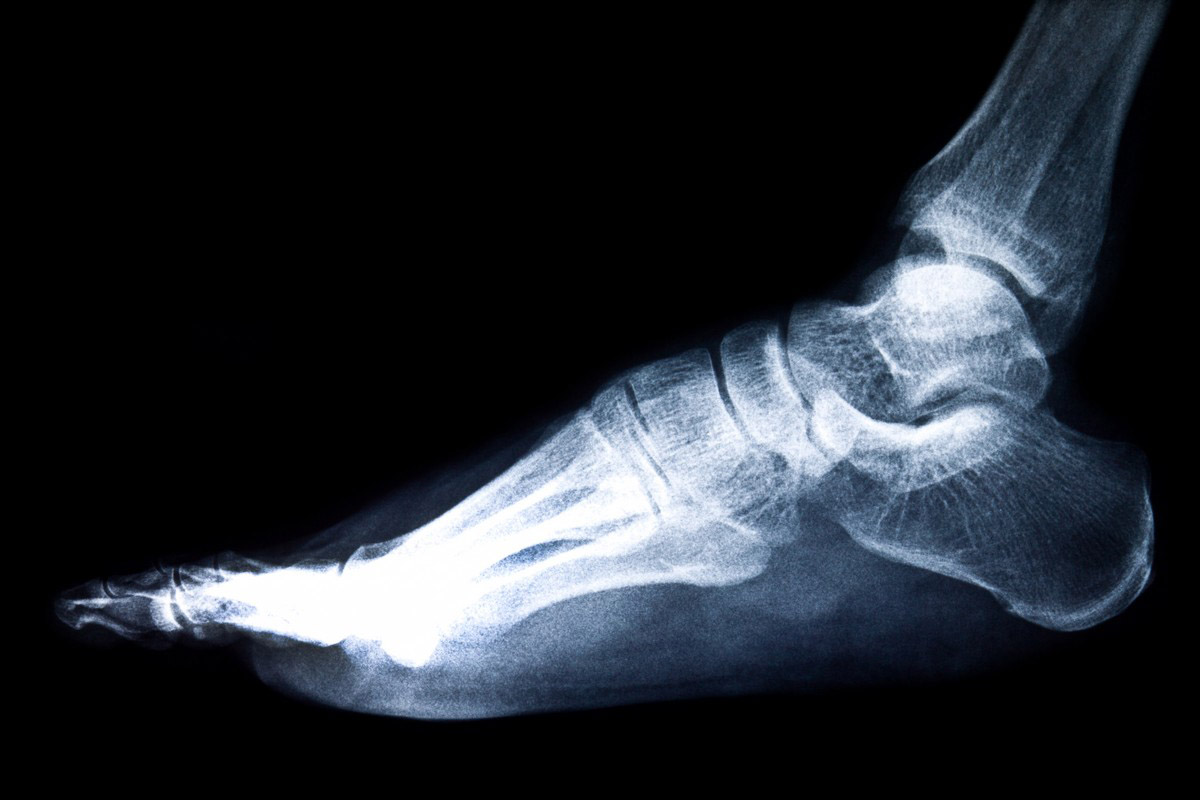

Перелом пяток

Пяточная кость считается достаточно прочной, поэтому ее переломы встречаются довольно редко. Чаще всего их причиной становятся тяжелые травмы, которые требуют продолжительного и сложного лечения и реабилитации. Многие пациенты, у которых был перелом пяток, обращаются к врачам с вопросом, когда перестанет болеть нога. Во время терапии иногда развиваются осложнения, но даже если этого не произошло, дискомфорт еще долго беспокоит. Для того чтобы от него избавиться, необходимо устранить атрофию мышц, восстановить кровообращение и повысить эластичность связочного аппарата. Пройти реабилитацию и справиться с болью можно только с медицинской помощью. Записаться на прием

Лечение травматического повреждения пяточной кости может выполняться с помощью консервативных и хирургических методов. Выбор той или иной тактики зависит от тяжести перелома, возраста пациента, его физиологических особенностей. Чаще всего осложнения возникают именно в тех случаях, когда применяли хирургическое лечение.

Наиболее информативным методом исследования, позволяющим оценить состояние мягких и костных тканей, получить трехмерное изображение стопы, а также понять, когда перестанет болеть после того, как был перелом пяток, является МРТ. Стоимость процедуры составляет около 2500-7000 рублей.

Перелом пятки — серьёзная травма, требующая немедленного обращения к травматологу. Промедление с началом терапии усиливает риск деформации стопы и нарушения походки. Считаю необходимым проведение рентгенографии или КТ для точного определения характера повреждения. Диагностика проводится с учётом механизма травмы и болевого синдрома. Также важно оценить способность к нагрузке и уровень отёка. Без помощи возможны нарушения функции стопы и хромота.